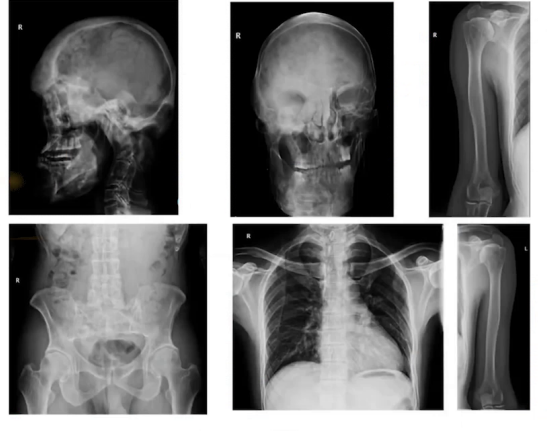

足月顺产出生,自幼身材略矮小,青春发育约在13-16岁。14岁起出现颅面部骨骼肿胀畸形,青春期加重。2010年当地医院CT提示左侧下颌骨髁状突及左侧颧骨眶下外侧壁骨质膨大等,诊断为左侧下颌骨颧骨骨纤维异常增殖症,行颧骨下颌骨肿物切除术,未见病理报告,术后畸形仍进展。2011年篮球撞击颈部后,MRI示上颈椎损伤、齿状突基底部骨折。

2024年1月,降糖方案调整为二甲双胍联合瑞格列奈。患者到我院就诊时,颈部活动受限,张口困难,左侧髋部和膝关节活动有摩擦感,有心悸,无其他特殊症状,食欲睡眠及大小便正常。2024年4月外院颈部CT显示下颌骨、颅面骨及颈椎有骨纤维异常增殖症表现。

入院查体生命体征平稳,头颅畸形不对称,下颌前凸、前额突出、口周凹陷,前额皮肤有散在褐色斑点,左眼球轻度前凸,颈部活动受限,甲状腺Ⅲ度肿大,质地稍韧,心肺腹查体未见异常。

垂体核磁共振平扫和增强正常,骨纤维异常增殖相关检查部分指标有变化。肋骨检查发现部分前肋骨骨质稍有膨大,骨盆及四肢骨未见明显病变。

1)骨纤维异常增殖症,4岁起颅面部骨骼畸形,青春期加重,手术未改善,还出现颈椎损伤及高位颈髓压迫合并变性,血钙磷基本正常,部分骨代谢指标异常;2)内分泌方面,2016年诊断甲亢,长期口服赛治,颈部增粗,甲状腺相关抗体正常,彩超见双侧多发结节且增大,其他内分泌激素评估正常;